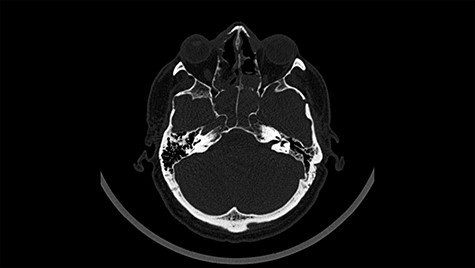

Head CT after polypectomy—seen sphenoid sinus and both maxillary sinuses filled with blood. (Department of Neurosurgery own material).

In described case, a head CT scan after polypectomy confirmed the subarachnoid hemorrhage (Fig. 1). In addition, the presence of air in the ventricular system was visible, and presence of defects of the upper left orbital wall and ethmoid on both sides (Fig. 3). In the CT scan sphenoid sinus, frontal and ethmoidal sinuses on both sides and right maxillary sinus airless, filled with blood and soft tissue. The changes also concerned the lateral part of the left maxillary sinus (Fig. 4).